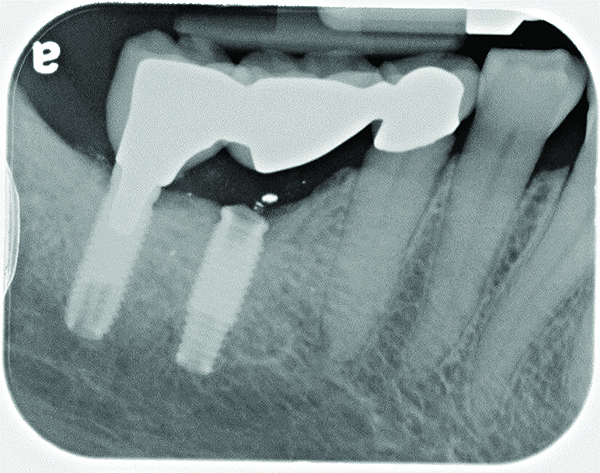

Implant related complications may be classified as minor, intermediate, major reversible/nonreversible, or major nonreversible. For example, a simple complication like a fractured abutment screw is usually considered a minor complication. It usually can be corrected with minimal cost, time, pain, and inconvenience. Treatment may be more involved for an intermediate complication such as a fractured implant (Figure 1). Up the severity scale are major complications, such as when an implant migrates into the sinus2 (Figure 2), or is exposed by mucosa and bone loss and visible to the patient a year after restoration (Figure 3 and Figure 4). Major complications may cause irreversible damage and/or require multiple procedures to try to make the patient “whole,” adding cost, time, pain, and surgeries (Figure 5 and Figure 6), and the patient may or may not receive the original restoration.

The implant of the patient shown in Figure 8 demonstrated all three of the red flag situations: it was placed too far buccally, had inadequate bone and soft tissue at the time of implant placement, and lost bone and soft tissue post implant placement. Correcting this required increased time, cost, and surgeries (Figure 9).

A implant restoration with a buccal dehiscence of bone and soft tissue caused by poor implant positioning, lack of keratinized tissue prior to implant placement, and soft tissue recession post implant restoration.

Figure 8

The same implant in Fig 8, 7 years following treatment, which included two autogenous connective tissue grafts and a bone augmentation surgery with a combined allograft and xenograft mixed with two biologics.

Figure 9